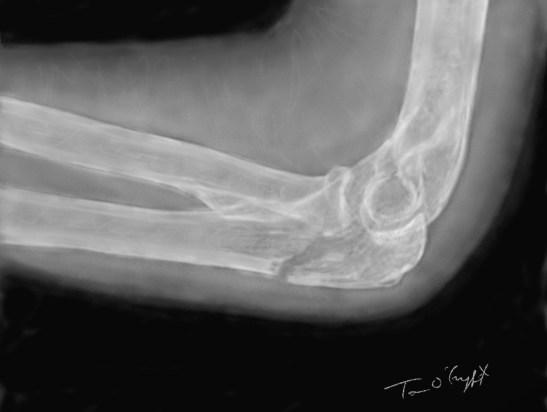

fracture de l’olécrâne peu déplacée sur une radiographie de profil du coude

La radiographie, notamment le profil, montre bien le trait de fracture. Souvent cette fracture est déplacée, car le fragment supérieur est tiré par le tendon du triceps brachial.